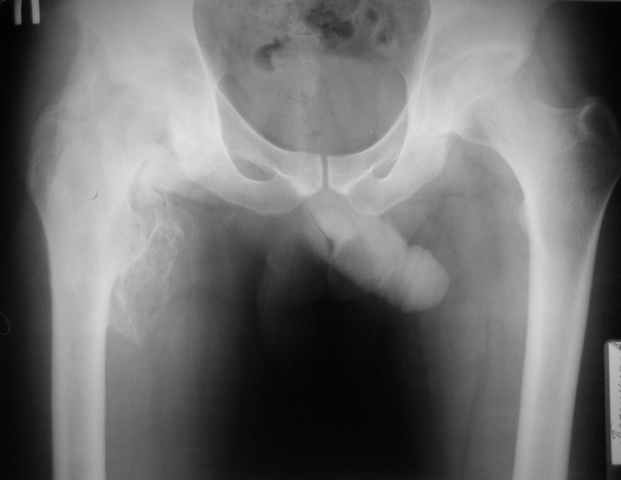

Уважаемые коллеги, здравствуйте! Пациент 1987 года рождения, сочетанная травма (ЗЧМТ, перелом костей голени) в январе 2010 года.

Около месяца на ИВЛ, В настоящее время неврологически компенсирован, ходит с ходунками, адекватен. Основная жалоба - отсутствие движений в тазробедренном суставе. Клинически наружная ротация 30 гр. умеренная мышечная атрофия, движения качательные. Рентгенологически-выраженные гетеротопические оссификаты в области правого тазобедренного сустава. Помогите определитсья с тактикой:Эндопротезирование? Сроки? Особенности. Заранее спасибо

Больной прооперирован. Передвигается самостоятельно при помощи костылей, продолжает ЛФК. Функциональные результаты ниже.

igor 18 Август 2010, 07:28

неделя после операции

igor 18 Август 2010, 07:32

около 1 недели после операции